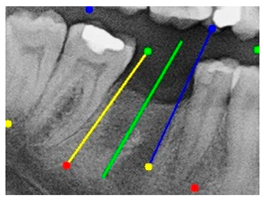

The angle bisector of the two auxiliary lines was then calculated using the angle bisector formula shown in (8), where (, , ) and (, , ) represent the coefficients of the two lines. The resulting internal angle bisector defines the preliminary implant pathway orientation derived by this framework. This bisector represents the most stable implant pathway orientation direction, ensuring that the implant avoids adjacent teeth and critical anatomical structures while maximizing bone–implant contact area. Such orientation enhances osseointegration stability and prevents complications from improper angulation, such as malocclusion or uneven stress distribution. The visualization of this process and the algorithmic design are presented in Figure 8. Finally, the auxiliary pathway generated by the algorithm was compared and overlapped with the implant pathway orientation annotated by dentists on the images to evaluate the predictive capability and accuracy of the model. The overlap results serve as a basis for further model optimization and provide valuable reference information for clinical application.

Figure 8.

Auxiliary lines are derived from adjacent teeth, the blue and yellow line is the result of implant pathway orientation visualization algorithm, and the green is the best implant pathway orientation.

3.3. Comparison with Clinical Ground Truth and AI-Assisted Framework

This subsection presents a comparison between the dentist-defined clinical gold standard and the predictions generated by our AI-assisted framework to evaluate the reliability of implant pathway orientation. The result is shown in Table 10, the preserved DPR validation set was used for verification, and the AI-assisted framework results were overlaid onto the original DPR images to provide a clear visualization. The AI-assisted framework pathways (green lines) were highly consistent with the dentists’ ground-truth annotations (black lines). Quantitatively, the mean squared error (MSE) between the predicted implant direction and the dentists’ planned results was only 1.537° across multiple test images. This minimal deviation validates the proposed system’s technical feasibility. It highlights its clinical potential to provide accurate and stable guidance for implant placement, thereby reducing the risk of misalignment and supporting efficient preoperative orientation.